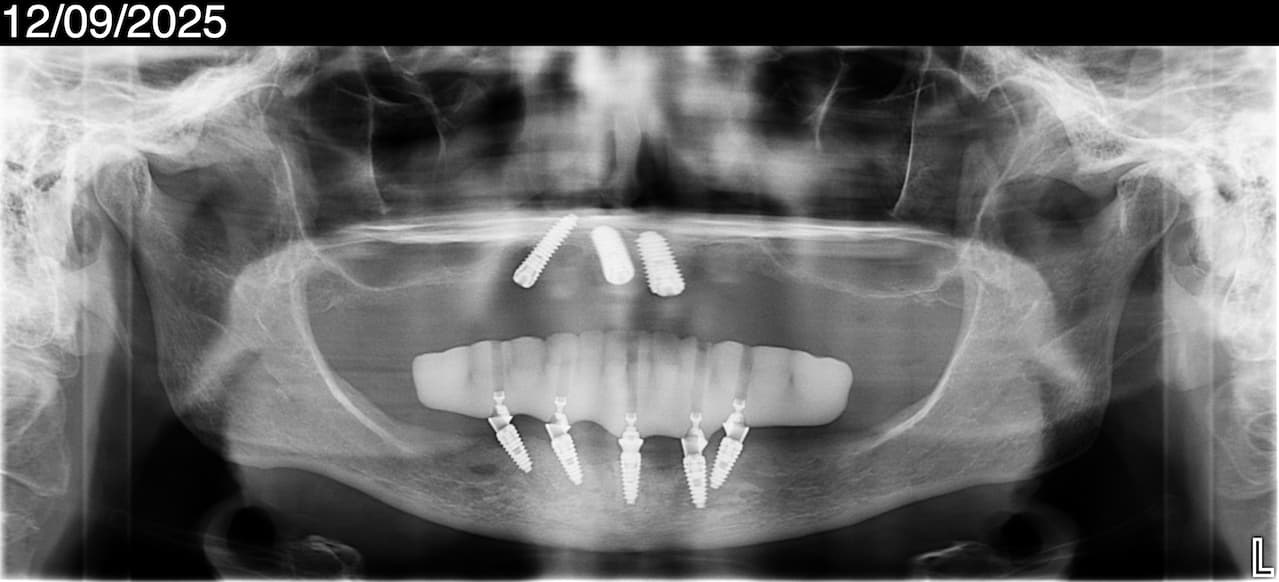

⚠ DISCLAIMER: Implants on the top and bottom were placed by another local dentist in September 2025. The patient was promised an upper and lower All-on-4 dental implants with Zirconia finals and paid $24,000. She shared that she never had the opportunity to meet a doctor either during the consultation or on the day of surgery.

The patient was put to sleep and woke up with 5 lower implants and 3 upper implants. She was given an upper REMOVABLE denture that she couldn’t wear, and the dentist had to remake it three times to make it comfortable for her. Even then, the patient ended up using her old denture because it felt better. She mentioned they just recently (2 full months after surgery) delivered her lower temporary bridge. Luckily, the patient came to our office, seeking a second opinion from our experienced and empathetic team of implant specialists.

This patient started out not having enough bone already on the upper jaw. Having worn the denture for many years, she hardly had any bone left. This was a pterygoid/zygomatic/anterior implant case to begin with, All-on-6 dental implants. And potentially a subperiosteal implant case.

The treating dentist misdiagnosed this difficult situation or, more likely, was going by the “seat of the pants” on the day of the surgery, having just seen her CT scan for the first time when the patient was already asleep.

Can these 3 implants on the top be restored? This is a big question, as they are only partially in the bone. If we remove these 3 implants, the patient will have no bone for dental implants. So, a subperiosteal implant solution is probably the way forward for her.